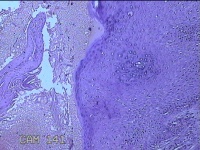

性别

男

年龄

45岁

临床诊断

皮下结节

一般病史

发现左侧一结节,伴局部瘙痒不适1年。

标本名称

左侧结节

大体所见

灰白暗红色带皮肤样结节0.8x0.7x0.3cm一个,表面糜烂,切开结节呈实性,切面灰白粉红色,质软。

图1

感觉像表皮样囊肿?